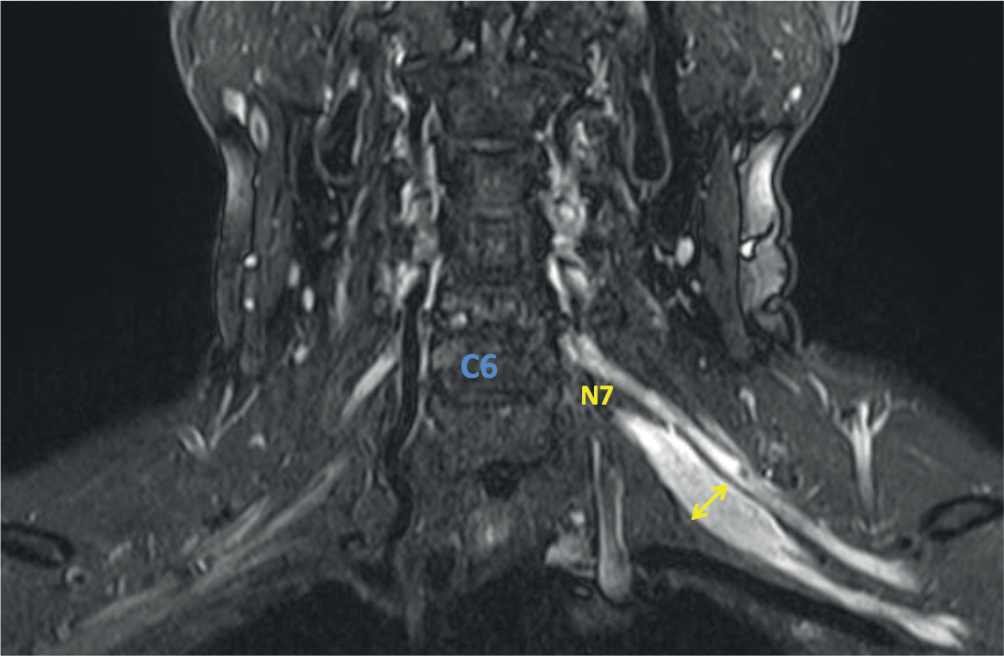

Рис. 4. МРТ ПС пациента с мХВДП (катамнез 6 лет, проводится поддерживающая терапия внутривенным иммуноглобулином в дозе 1 г/кг 1 раз в 12 нед в течение 2 лет). В режиме STIR в коронарной проекции справа определяется диффузное выраженное утолщение N7 до 12 мм, сопровождающие повышением МР-сигнала. Повышение МР-сигнала отмечается и от других элементов ПС справа на всём видимом уровне без изменения толщины. Слева изменений нет.

Fig. 4. MRI of BPs in a MADSAM patient (6-year follow-up history; assessed on maintenance therapy: intravenous immunoglobulin 1 g/kg every 12 weeks for 2 years). The coronal STIR MRI showed right-sided significant (≤ 12 mm)

diffuse N7 thickening, with hyperintense signal. Hyperintense MRI signals from other right-sided BP elements were registered at the entire visible level with unchanged thickness. No changes on the left side.